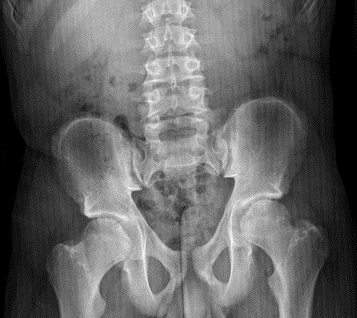

Se realiza estudio de talla baja: bioquímica con perfil hepático, renal y tiroideo normal; anticuerpos antitransglutaminasa negativos; perfil hormonal (IGF1: 213 ng/ml, IGFP3: 4,6 ng/ml, insulina basal: 3 mcU/ml, LH: 2,7 mUI/ml, FSH: 2,34 mUI/ml) con valores normales para edad y sexo; edad ósea de 13 años (que se corresponde con la EC). A la vista de los resultado analíticos normales y de las características de la exploración física, se solicita un estudio radiográfico completo donde se aprecia platispondilia, hiperlordosis lumbar, escoliosis leve (ángulo de Cobb menor de 20°) y dismetría de miembros inferiores (Figuras 1 y 2). Ante la asociación de talla baja desproporcionada de manifestación tardía y las anomalías esqueléticas descritas, se sospecha displasia espondiloepifisaria tardía y se solicita estudio genético, obteniéndose la variante patogénica c.93+5G>A en el gen TRAPPC2 en homocigosis, ligada al cromosoma X. Se realiza estudio genético familiar, siendo la madre portadora de la misma mutación.

Figura 1. Radiografía anteroposterior de pelvis: ensanchamiento de la cabeza femoral bilateral y dismetría de miembros inferiores (derecho acortado). Mostrar/ocultar